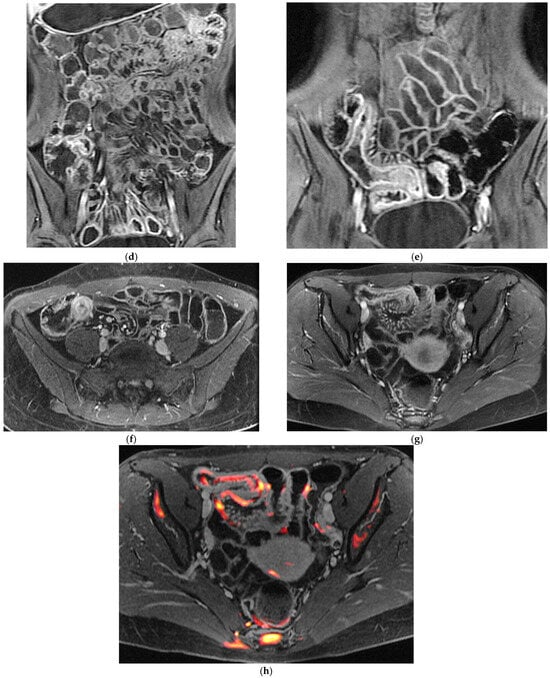

Figure 2.

47-year-old female patient with recurrent ileal Crohn’s disease following resection. (a) Coronal T2-weighted image demonstrating recurrent ileal Crohn’s disease at the anastomotic site, characterized by marked bowel wall oedema. (b) Corresponding axial T1-weighted image after gadolinium administration showing intense mural hyperenhancement of the affected ileal loop. (c) Post-processed color-coded map derived from the T1-weighted gadolinium-enhanced sequence, with areas of maximal enhancement highlighted in red. (d) Single-shot fast spin-echo sequence with follow-through–like appearance, clearly depicting the lumen of both normal and pathological small-bowel loops. (e) Axial diffusion-weighted imaging (DWI) showing marked diffusion restriction within the diseased ileal segment.

A major advantage of MRE, which strongly influences clinical decision-making, is its capacity to characterise strictures with exceptional detail. The ability to distinguish inflammatory from fibrotic narrowing relies on the multiparametric information inherent to the technique: active inflammatory strictures typically demonstrate high T2 signal, prominent or layered enhancement, and restricted diffusion, whereas fibrotic strictures often appear as low-signal, homogeneous, and relatively non-enhancing segments with preserved diffusion characteristics [12,20,21]. This distinction is critical, as treatment of inflammatory strictures favours medical escalation—including biologics—whereas fibrotic strictures often require endoscopic or surgical intervention.

MRE is equally valuable in the detection of penetrating complications, an area where its sensitivity rivals or surpasses that of CT [14]. MRE is particularly effective in identifying entero-enteric and entero-colonic fistulas, subtle sinus tracts, intramural or mesenteric abscesses, and inflammatory phlegmons. These complications carry significant prognostic weight, often predicting a more aggressive disease course and influencing therapeutic strategies. Because MRE enables both mural and extramural structures comprehensively, it provides a more complete assessment of disease behaviour than endoscopy alone [9] (Figure 1 and Figure 2). The diagnostic performance of MRE has been validated in several prospective comparative studies [5,6,7,8,9,10,11,12,13,14,15,16,17], such as the multicenter METRIC trial, showing a sensitivity of approximately 97% for detecting the presence of small-bowel Crohn’s disease and around 80% for defining disease extent [23]. In the same study, IUS demonstrated a slightly lower sensitivity for the detection of small-bowel disease (approximately 92–94%), a specificity comparable to that of MRE (both exceeding 90%), although the accuracy in defining the full extent of disease inferior to MRE (70%). Overall, while both modalities showed high diagnostic performance, MRE provided a superior sensitivity for disease presence and extent, particularly in the proximal small-bowel segment [23]. MRE also showed high accuracy in identifying active inflammation and extramural complications, consolidating its role as the reference cross-sectional modality for comprehensive small-bowel evaluation [8].